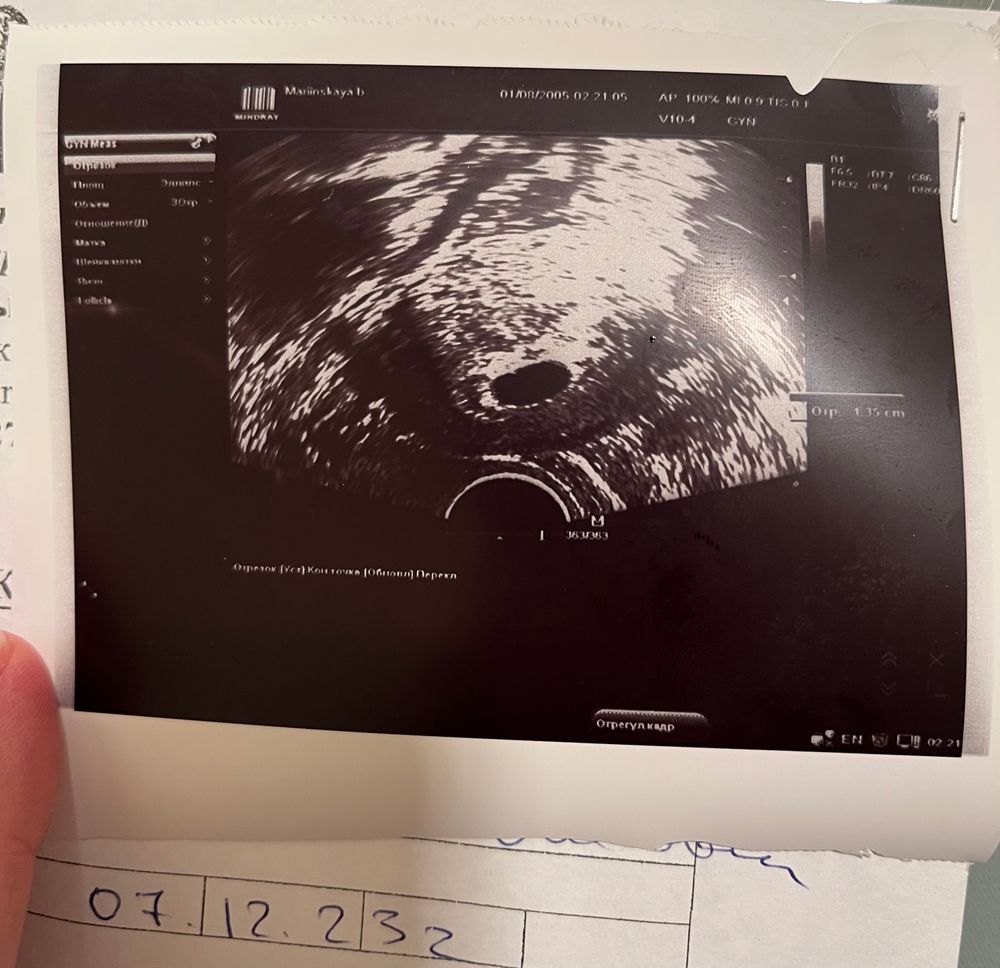

увидела только ПЯ 13,5 мм и все

но мне кажется я что-то вижу!!! Поддержку не отменила, буду ждать!!! Записалась завтра на экспертное узи! Посмотрите, видите что-нибудь?

Во первых "срочно" на МА точно не нужно. Если это первое УЗИ, обязательно переделать через неделю (а лучше сейчас проверить у другого узиста и динамику смотреть у него же потом). По фото действительно пусто сейчас. То что вы обвели на фото в комментариях это уже за пределами ПЯ. Но анэмбриония ставится при размерах ПЯ 20-25 мм, так что у вас шансы ещё есть, что все появится, чего вам и желаю 🙌